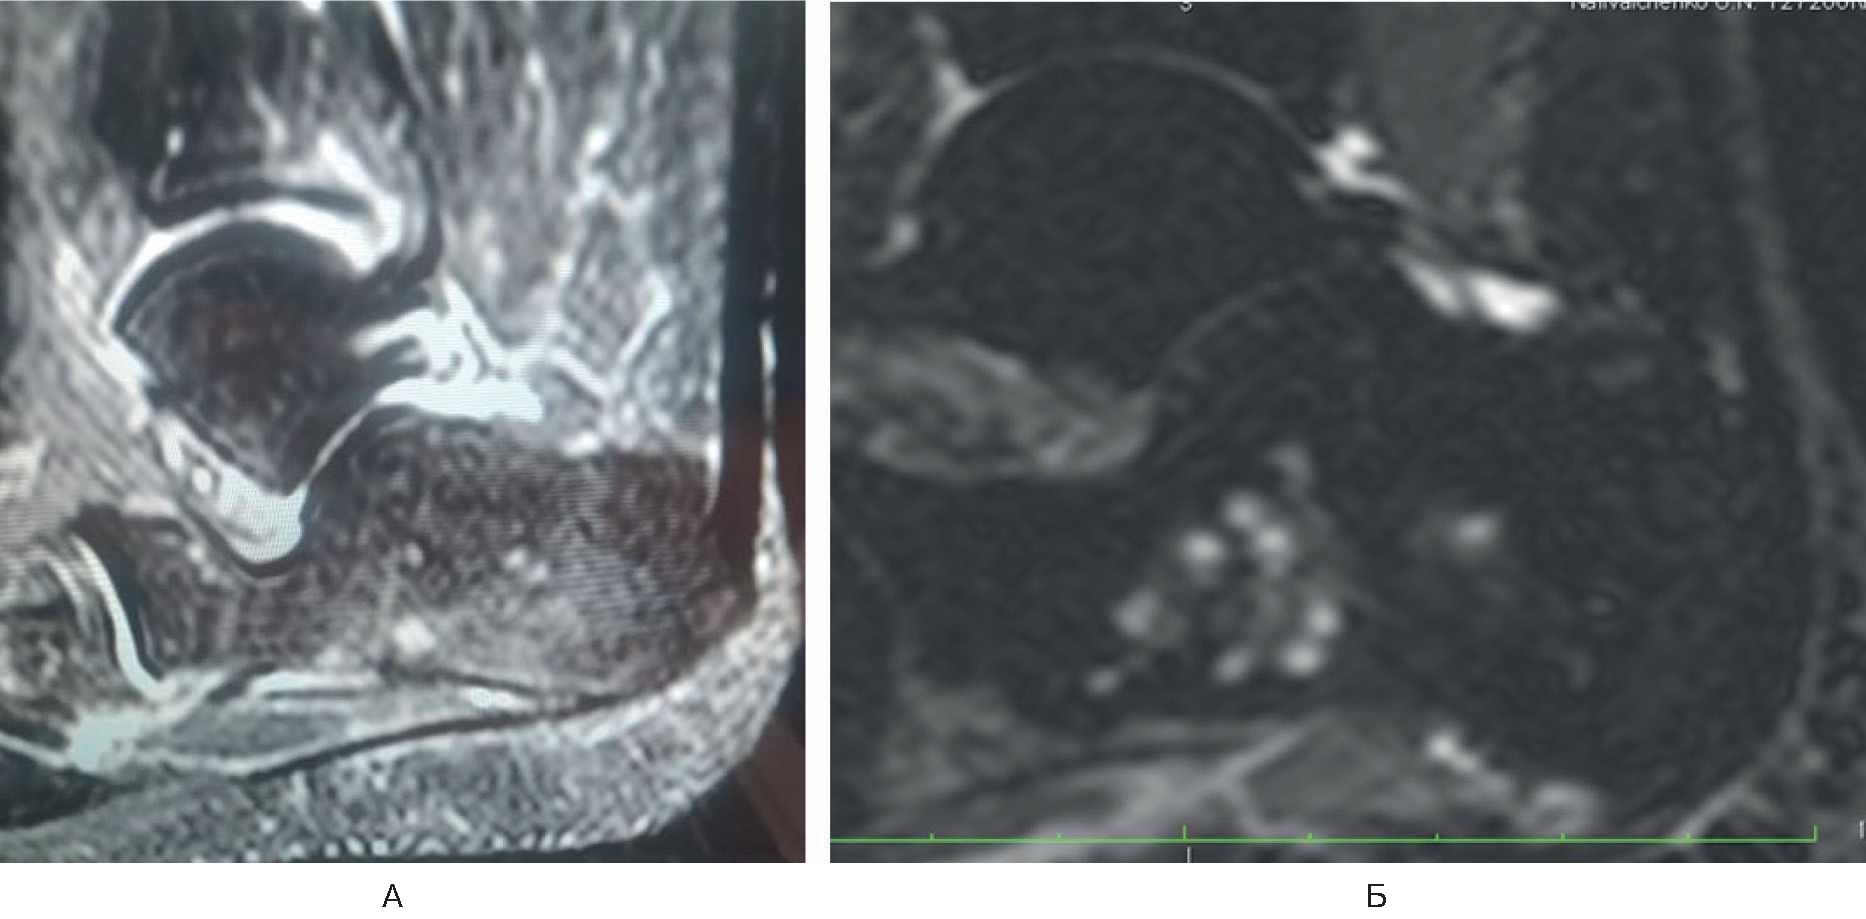

Лечилась у невролога консервативно с мая по сентябрь 2021 г. без положительной клинической динамики, а с сентября по декабрь 2021 г. – у травматолога по месту жительства по поводу тендопатии. Положительной клинической динамики не было. В марте 2022 г. на приеме у ортопеда выполнена МРТ правой стопы, диагноз – асептический некроз тела пяточной кости (рис. 4А).

Рис. 4. МРТ правой стопы у пациентки Г.

В марте 2022 г. произведена транскутанная остеоперфорация тела правой пяточной кости. Назначен терипаратид 20 мкг подкожно 1 раз в сутки. МРТ-контроль через 1 мес. На контрольном осмотре: пациентка отмечает восстановление функции правой нижней конечности, отсутствие болевого синдрома в правой пяточной кости (0 баллов по ВАШ). По данным контрольной МРТ – положительная динамика, отсутствуют признаки асептического некроза (см. рис. 4Б).

Обсуждение. При изучении публикаций авторами статьи не получены убедительные данные о влиянии COVID-19 на развитие остеонекроза. X.H. Xie и соавт. приводят различные механизмы остеонекроза, включая аномалию

А – асептический некроз тела пяточной кости; Б – отсутствие признаков асептического некроза.